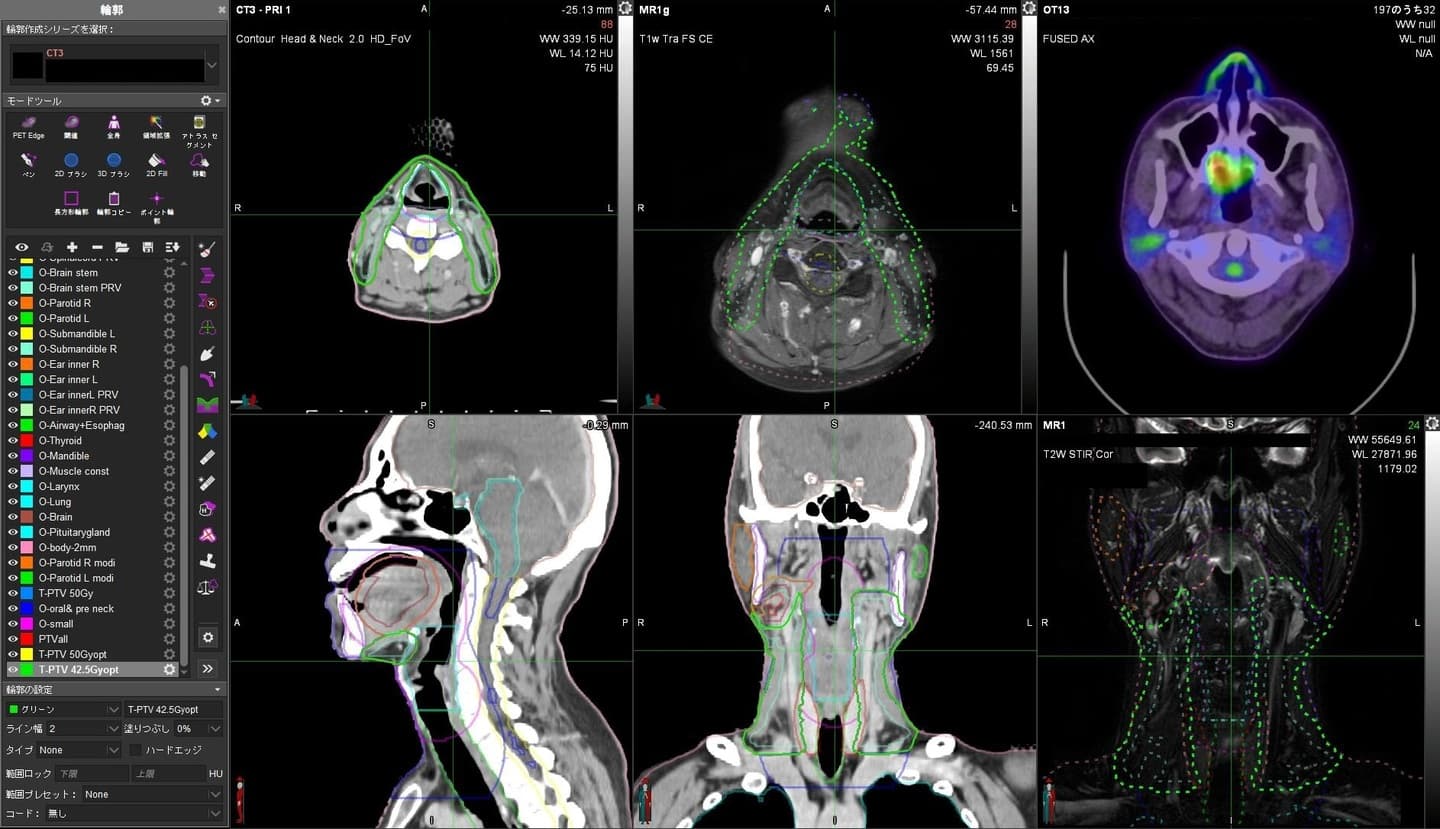

治療計画装置, 治療計画支援装置

Eclipse ver.15.6(VARIAN) 3台

RayStation ver.6(RaySearch) 1台

iPlan ver.4.5.5(Brain Lab) 2台

MIM maestro ver.7.1.4(MIM) 2台